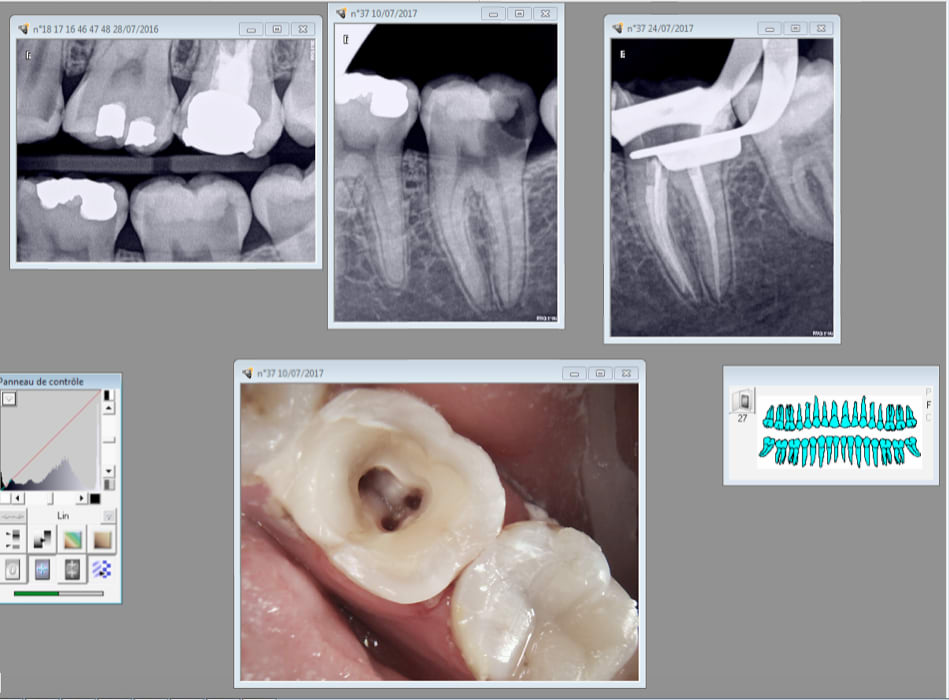

Je devance la réflexion de casa qui pense que je sors mes R25 pour un oui ou our un non par un exemple qui illustre la vie quotidienne au cabinet. Cas extrême, mais relativement fréquent, qui illustre la parfaite dé responsabilisation des patients en France qui ne consultent en général qu'à l'occasion de signes d'appels hormis ceux qui on besoin d'une attestation. Attestation en vue d'une intervention chirurgicale ou attestation de bonne santé buccodentaire par exemple pour les militaires. On voit aussi des femmes enceintes depuis l'idée lumineuse du BBD qui tombe pile poil au moment propice pour faire des soins. -)

Donc patiente vue en urgence pour une pulpite sur 46 il y a un an, ouverture chambre . Le 10 juillet de cette année consulte en urgence pour une pulpite mais sur la 37. Je la prends ouverture chambre et RDV aujourd'hui pour l'endo et miracle ! elle est venue. J'en ai profité pour virer la 46 dans la foulée. -) J'y ai collé un IRM ( on ne sait jamais lol !) Et peut etre qu'un jour on aura l'occasion de faire une couronne et de soigner les autres caries qu'elle a en bouche si elle n'oublie pas à nouveau de prendre RDV en septembre. . Je prends mes vacances au mois d'aout elle est venue le 28 juillet 2016 en urgence et zappé de prendre un RDV pour terminer les soins en septembre. Le fait d'avoir un trou béant dans la 46 pendant un an ne l'a pas interpellée plus que ca.